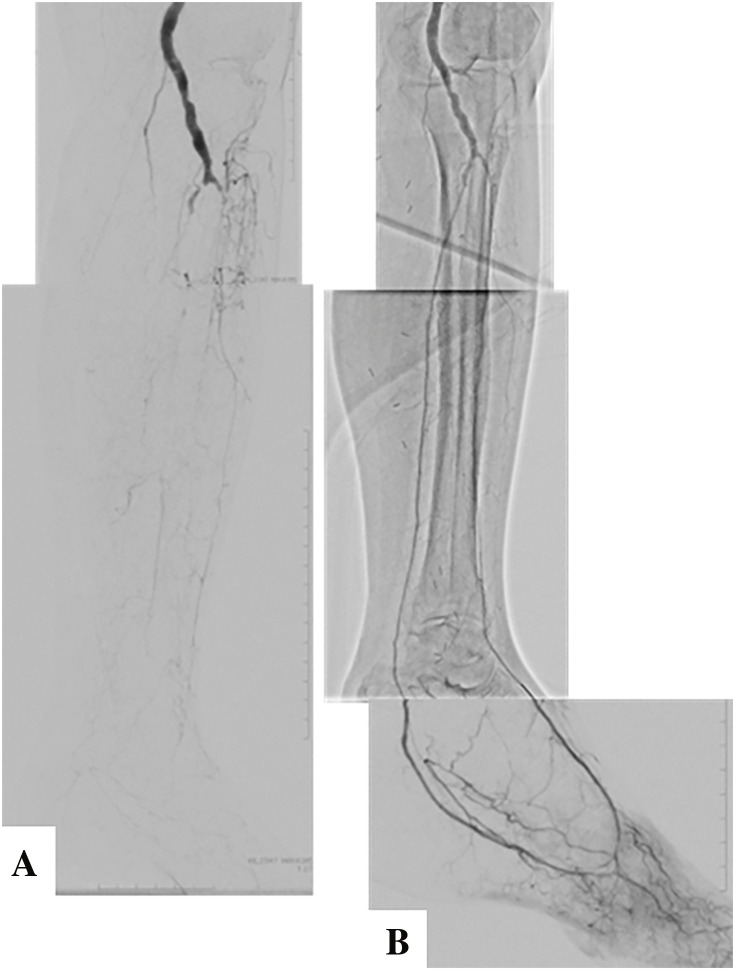

Infrapopliteal revascularization is generally performed for patients with chronic limb-threatening ischemia. As with revascularization in other fields, the indications for endovascular treatment (EVT) have expanded in recent years due to advances in endovascular devices and techniques. However, the optimal revascularization method must be selected based on (1) patient risk, (2) limb severity, and (3) anatomical pattern of disease. Therefore, vascular surgeons need to understand the characteristics of EVT and surgical treatment and improve their technical skills in both procedures. Here is an overview of the current methods of revascularization. (This is a translation of Jpn J Vasc Surg 2024; 33: 61-65).